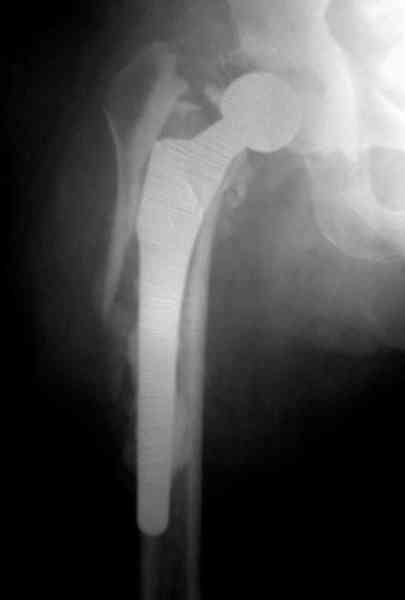

Представляю вашему вниманию снимки (прошу прошения за качество снимков) больной 48 лет с ревматоидным артритом, которой был сделан тотальный эндопротез справа,

контрольный снимок сделали только на 21 день после операции (№1) и с интервалом 5 дней второй снимок (№2)

Первичные снимки не сохранены.